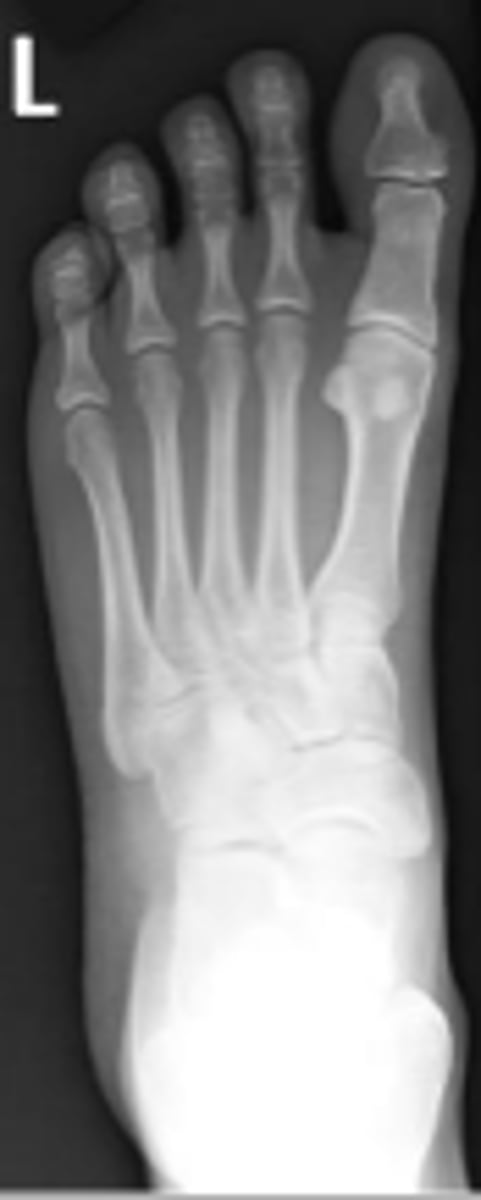

Medial oblique of the left foot

What is the name of the radiographic view?